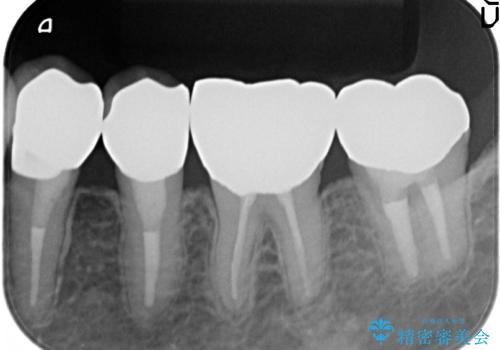

- 左下4番目の歯がなにもしなくてもズキズキ痛むので診て欲しいといらっしゃった方の症例です。

検査の結果、神経の保存は難しかったため、根管治療を行った後オールセラミッククラウンによる補綴を行いました。

今回用いたオールセラミッククラウンはジルコニアフレームという白い素材の上にセラミックを盛っているため、審美性が非常に高いのが特徴です。

また、ジルコニアは人工ダイヤモンドの材料にも使われているほど高い強度を持っており、そのためオールセラミッククラウンは審美性だけでなく、奥歯やブリッジの補綴も可能とするクラウンです。